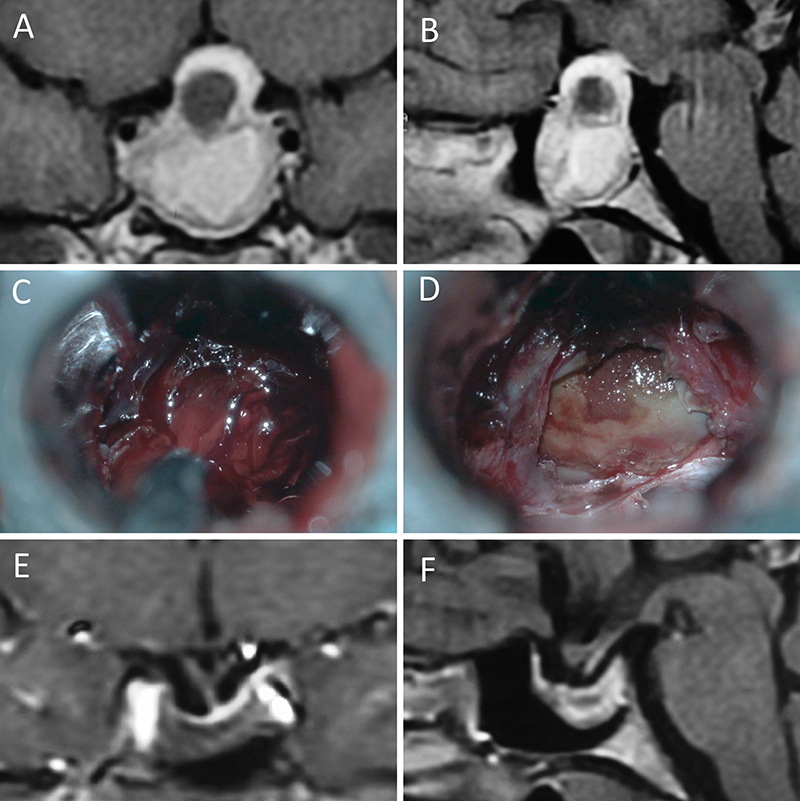

Figura 1: Macroadenoma no funcionante en mujer de 65 año s. Se decidió la cirugía tras evidenciarse crecimiento en los controles. Evolucionó favorablemente desde el punto de vista clínico-radiológico. A-B: RM preoperatoria; C-D: intraoperatorio; E-F: RM postoperatoria.

Figura 2: Macroadenoma no funcionante en mujer de 31 años. La paciente presentó en el preoperatorio déficit visual que mejoró tras la cirugía. A-B: RM preoperatoria; C-D: intraoperatorio; E-F: RM postoperatoria.

Figura 3: Macroadenoma no funcionante en un hombre de 64 años. El paciente presentó en el preoperatorio déficit visual que mejoró tras la cirugía. A-B: RM preoperatoria; C-D: intraoperatorio; E-F: RM postoperatoria.

Figura 4: Macroadenoma no funcionante en mujer de 32 años. La paciente presentó en el preoperatorio déficit visual que mejoró tras la cirugía. A-B: RM preoperatoria; C-D: intraoperatorio; E-F: RM postoperatoria.